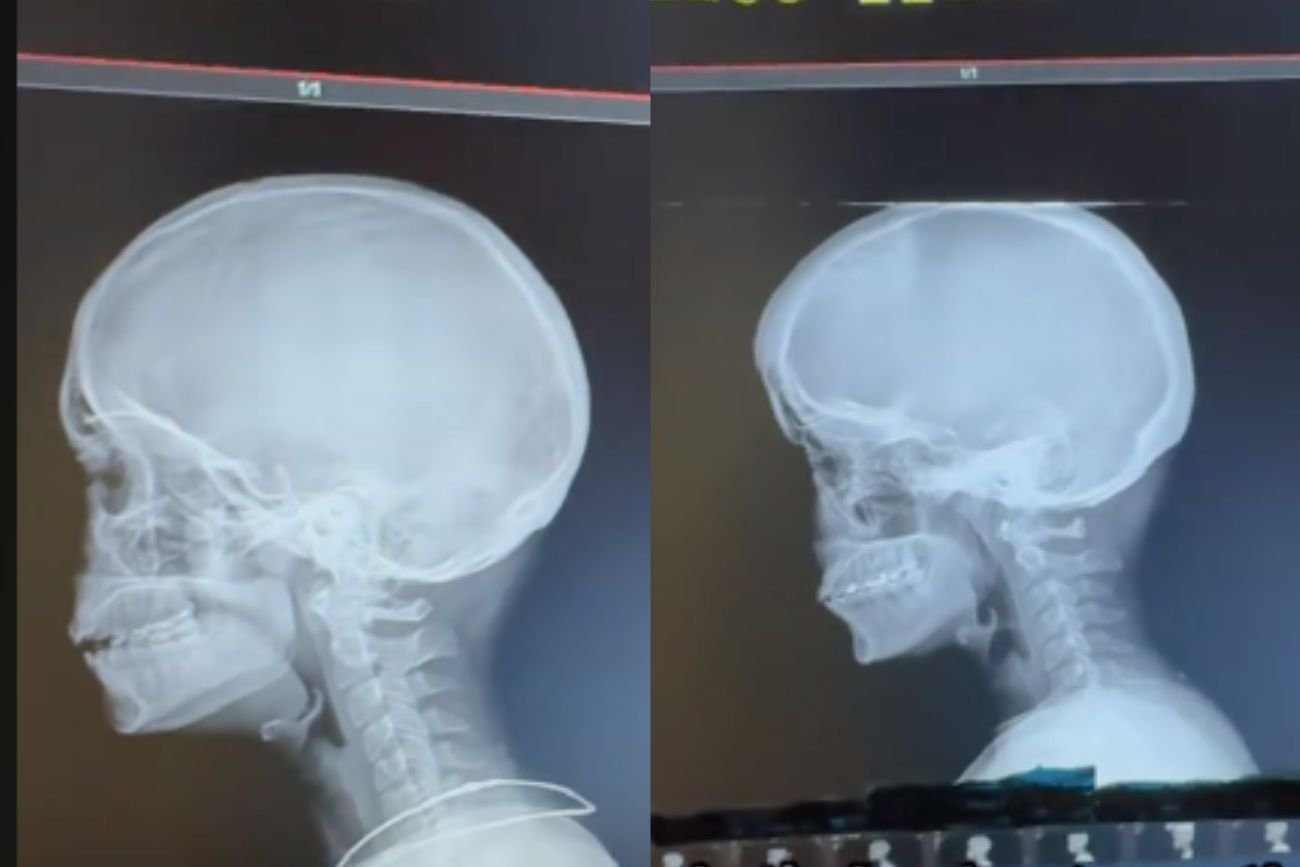

– Jeśli masz mniej niż 35 lat, lepiej się teraz skup – tymi słowami chiropraktyk z TikToka zaczął swój film. A potem pokazał zdjęcie rentgenowskie 13-latka (!) w początkowej fazie artretyzmu. Na co dzień pracuję w pozycji krewetki, ale po obejrzeniu tego 2-minutowego filmu momentalnie się wyprostowałam.

Nieważne, ile masz lat. Ten film dobitnie pokazuje, co dzieje się z naszymi kręgosłupami, jeśli większość dnia spędzamy zgarbieni, wpatrzeni w ekrany telefonów czy komputerów. Pokazuje, co dzieje się z kręgosłupami dzieci – dzwonnik z Notre Dame to porównanie, które nasunęło mi się jako pierwsze.

Dr Jake Boyle, chiropraktyk z Des Moines (Iowa, USA), rozbił bank swoim wiralowym filmem na TikToku. Pokazał w nim kilkanaście zdjęć rentgenowskich osób poniżej 35. roku życia – milenialsów, przedstawicieli pokolenia Z i jednej 13-letniej alfy.

Skrzywienie kręgosłupa i rosnący garb spowodowane ciągłym pochylaniem się (najpewniej nad smartfonem) to jedno. Na niektórych zdjęciach kręgarz wskazał narośl u podstawy czaszki przypominającą róg. O zewnętrznym guzie potylicznym u młodzieży pisałyśmy już w 2019 roku – niedługo po publikacji badań naukowców z Uniwersytetu Sunshine Coast w Queensland w Australii, którzy wykazali, jak nadmierne korzystanie z nowych technologii deformuje ludzki szkielet.